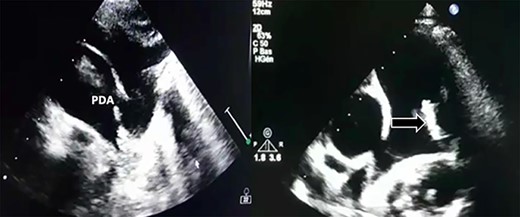

Transthoracic echocardiography revealed a large PDA (10 mm) with left-to-right shunt and a fixed structure on the wall of the pulmonary artery, with erratic movement indicative of a vegetation (Fig. 1), and mobile vegetation attached to the wall of the descending aorta in the supra-sternal view (Fig. 2) and a left ventricle with conserved systolic function and 55-mm end-diastolic diameter.

Supra-sternal view: vegetation attached to the wall of the descending aorta.